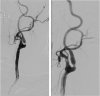

Samotného uzávěru aneuryzmatu lze dosáhnout dvěma způsoby: chirurgicky – naložením svorky přes vstup do výdutě; a endovaskulárně – radiolog pomocí speciálních tenkých hadiček pronikne tepenným řečištěm přímo do výdutě a speciálními spirálkami ji vyplní. Rozhodnutí, které řešení je vhodné pro konkrétní výduť a pacienta, vyplyne z mezioborové diskuze zohledňující nejen výše zmiňované faktory. Po vyřazení aneuryzmatu z oběhu je pacient dlouhodobě sledován pomocí CT či MR angiografie – cílem je odhalit případnou recidivu v původní oblasti či nově vzniklou výduť na jiném místě mozkové cirkulace.